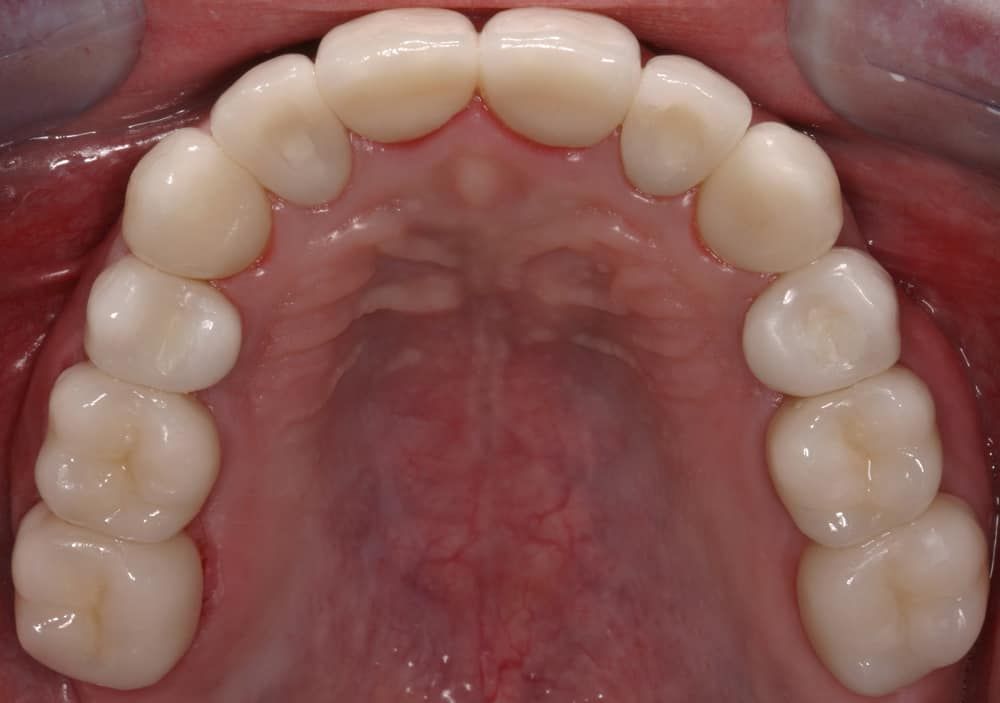

Case Study Details

Congenitally Missing Teeth; Full Mouth Reconstruction/Rehabilitation; Increased Occlusal Vertical Dimension; Pre-Orthodontic Treatment; Ceramic Crowns-bonded; Implant Crowns

After:Â Implants were then placed by the team oral surgeon utilizing surgical guides fabricated by Dr. Leopardi. Dr. Leopardi then performed a complete dental (full mouth) rehabilitation: full coverage, conservative bonded porcelain restorations on natural teeth; all ceramic implant restorations on the upper lateral incisor implants (sited 7 and 10), porcelain fused to gold implant restorations on implants 3, 14, 19, 21, 23, 25, 28 and 29, at increased occlusal vertical dimension. Patient was restored to full function and aesthetics, significantly improving quality of life.